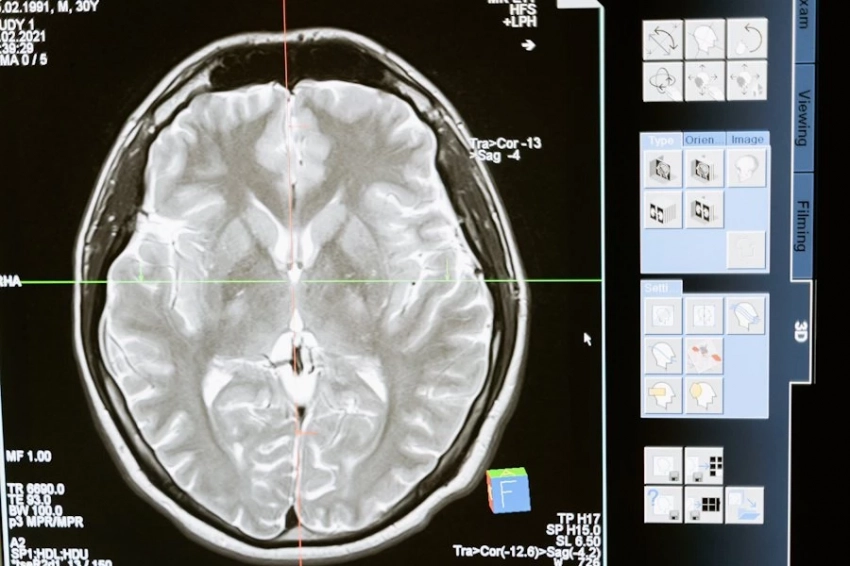

Как сообщает пресс-служба программы «Приоритет 2030» Минобрнауки РФ, в рамках которой ведутся исследования, специалисты БФУ имени Иммануила Канта разработали и представили новый метод исследования нейронных связей на базе данных функциональной магнитно-резонансной томографии.

Чтобы создать нужный алгоритм, исследователи изучили показатели работы функциональных сетей головного мозга для здоровых людей и пациентов с депрессией, и на базе этого сравнительного анализа потом делали выводы о наличии или отсутствии болезни у обследуемых пациентов.